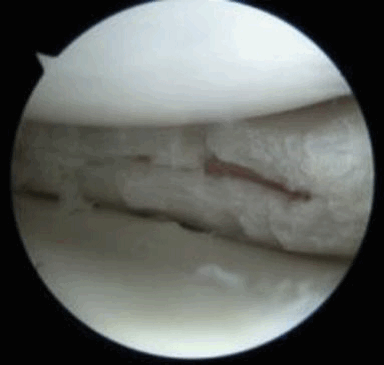

На снимке – разрыв крестообразной связки и мениска вследствие травмы колена

(Слева) На рисунке сагиттального среза показана центральная муцинозная дегенерация мениска вследствие нарушения образования коллагена и утраты целостности волокон. Линейный разрыв не отмечается.

(Справа) MPT PDBИ, режим подавления сигнала от жира, сагиттальный срез: у мужчины 74 лет определяется диффузный неясный гиперинтенсивный сигнал по всему заднему рогу медиального мениска. Тщательное изучение сагиттальных и коронарных изображений, включая короткие ТЕ последовательности (Т1ВИ или PDBИ) необходимо для исключения разрыва, распространяющегося на суставную поверхность мениска.

(Справа) MPT PDBИ, сагиттальный срез: определяется неровность/нечеткость свободного края заднего рога латеральною мениска. При артроскопии это может быть описано как изнашивание, неровность или разрыв. Необходим поиск других линейных разрывов.